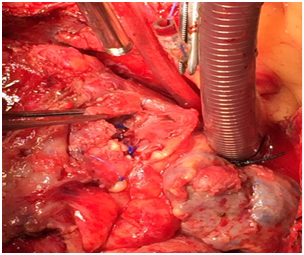

Surgical intervention was done with cardiopulmonary bypass. After Sternotomy, severe dense pericardial adhesion had been seen around the pseudoaneurysdm , adhesion was very carefully dissected, pseudoaneurysm was opened, palpated the stent on RCA, stent had been removed, endarterectomy was done in RCA distal to pseudoaneurysm, 2 small perforation in RCA was repaired by 6-0 polypropylene, RCA proximally and distally ligated with 4-0 polypropylene. Most of the wall of the Pseudoaneurysm had been removed and marsupialization was done. Venous graft was given to distal RCA after long endarterectomy (Figures 1–7).

Figure 2 Severe pericardial adhesions.

Figure 3 Pseudoaneurysm in right coronary artery.